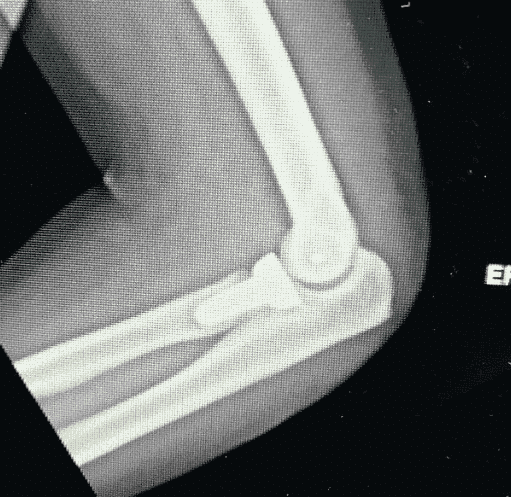

Types of Fractures From Car Accidents

If you’ve been in an accident and were treated by your doctor, you are probably already familiar with the exact type of fracture or broken bone you suffered as a result of the accident. Regardless, the most common types of fractures or broken bones we see in our office are: